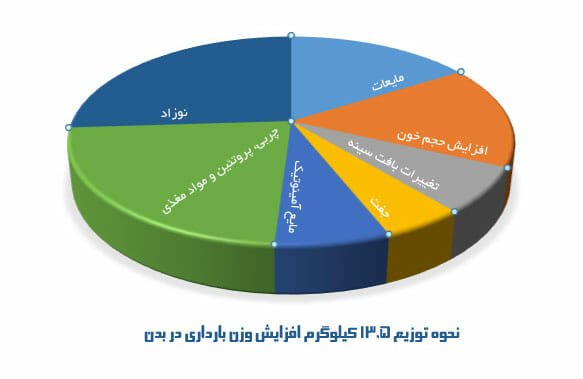

شاید تصور کنید که اضافه وزن دوران بارداری، به معنای انباشته شدن چربیها در بدنتان است. اما واقعیت این است که از حدود ۱۳.۵ کیلو گرمی که به طور متوسط زنان در این دوره اضافه میکنند:

- ۱.۵ تا دو کیلوگرم مایعات است؛

- ۱.۵ تا دو کیلوگرم ناشی از افزایش حجم خون است؛

- یک کیلوگرم به تغییرات بافت سینه مربوط میشود؛

- هفتصد گرم متعلق به جفت است؛

- یک کیلوگرم مایع آمینوتیک است؛

- ۳ کیلوگرم چربی، پروتئین و مواد مغذی ذخیره شده است؛

- ۳.۵ کیلوگرم هم وزن نوزاد شماست.